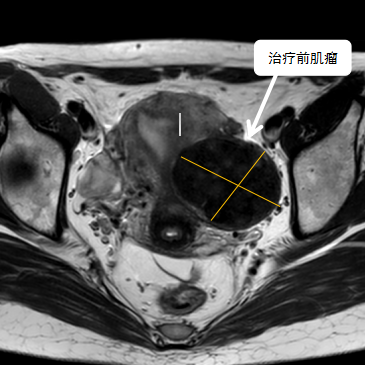

38歲的袁女士多年前發(fā)現(xiàn)子宮肌瘤,病情雖不嚴(yán)重,但是最近三年腫瘤在逐步增大,最大的肌瘤將近6公分,袁女士下一步面臨生育問題,如果不處理子宮肌瘤,懷孕期間激素水平的變化有可能會導(dǎo)致肌瘤快速增大;如果常規(guī)手術(shù)處理肌瘤,由于瘢痕粘……